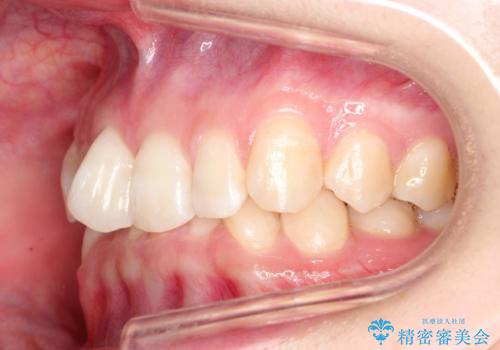

ハーフリンガル ワイヤー矯正による非抜歯・過蓋咬合の治療

- 非抜歯、大臼歯遠心移動による臼歯関係の是正・過蓋の改善をハーフリンガル・ワイヤー矯正にて計画した。